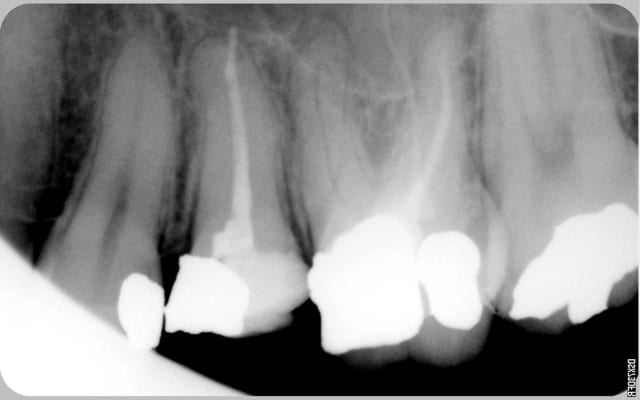

encore des radios,peut-etre assez moyen comme traitement...mais je vu pire...

les dernieres radios. patient en urgence ,abces... il voulait pas extraire la dent. j'ai lui bien explque et il a choisi de essayer de garder la dent. retrait,pas d'isolation avec la digue donc pas de tenon fibree,amalgam et screw post.traitement fait il ya 2 ans je crois.patient fidel de cabinet maintenent.

j'ai jamais utilise en roumanie l'amalgam et ca s'utilise pas du tout dans le cabinet du roumanie.